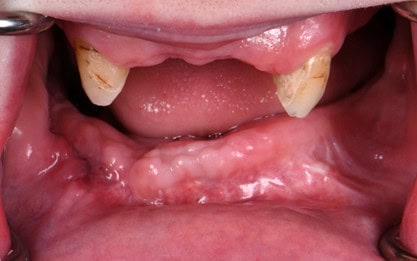

Two months later, the full prosthodontic evaluation revealed severely limited opening with an inter arch maximum distance of around 18mm (from alveolar ridge to ridge) (Fig. 2A and 2B). The maxillary tuberosities were 2mm superior to the retromolar pads bilaterally. The goal of maintaining the cuspids served as a reference during the mandibular repositioning and subsequent use as a potential abutment for future overdenture treatment.

Figure 2A: Intraoral photo at the time of the prosthodontic consultation. (have a few other pictures to choose from)